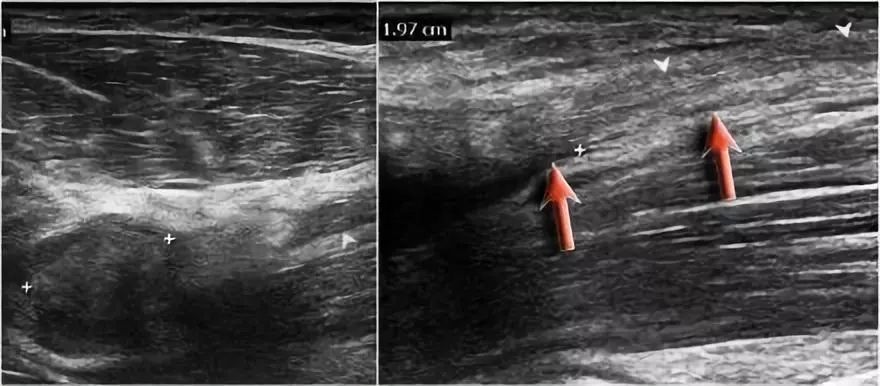

远端肱二头肌肌腱的病理学很像跟腱的病理学。可以有退变,部分撕裂和完全撕裂带或不回缩。以下是73岁男性的超声图像,他们在举起一个盒子时经历了突然的疼痛和撕裂的感觉。在肘关节前方有前旋和旋后疼痛,前方有压痛。

没有瘀斑或可触及的肿块。在矢状图像上,肌腱变厚,但远端肌腱丢失。

在矢状图像上,看起来肌腱完全是刺,但继续下一个图像。

● 远端肱二头肌肌腱撕裂:有完全撕裂,因为如果我们一直跟随肌腱进入桡骨结节,我们可以看到肌腱不附着在那里(绿色箭头)。只有流体。● 肌腱不缩回的原因是因为广泛的萎缩性肌腱 - 也被称为lacertus fibrosus - 仍然完好无损(红色箭头)。● 远端肱二头肌肌腱不仅插入到桡骨结节,而且还通过褶皱纤维进入前臂内侧屈肌旋前肌块的筋膜。

当腱膜也thorn时,肌腱缩回,并且由于收缩的二头肌造成手臂明显肿胀。远端二头肌肌腱撕裂是一种罕见的损伤。大约有5%的肱二头肌受伤。这是肘部弯曲时手臂突然伸展的结果。近端肱二头肌腱撕裂更常见。通常是二头肌的长头完全撕裂。

下面这是另一个例子。在T1W图像上有一些增厚和一些中间信号。这可能是肌腱变性,但总是看T2W图像寻找撕裂。在这种情况下,有部分撕裂。

下面是另一种情况。在矢状图像上,我们不确定可能的撕裂。也许只有一些肌腱炎或肌腱炎。轴向图像显示部分撕裂(红色箭头)。